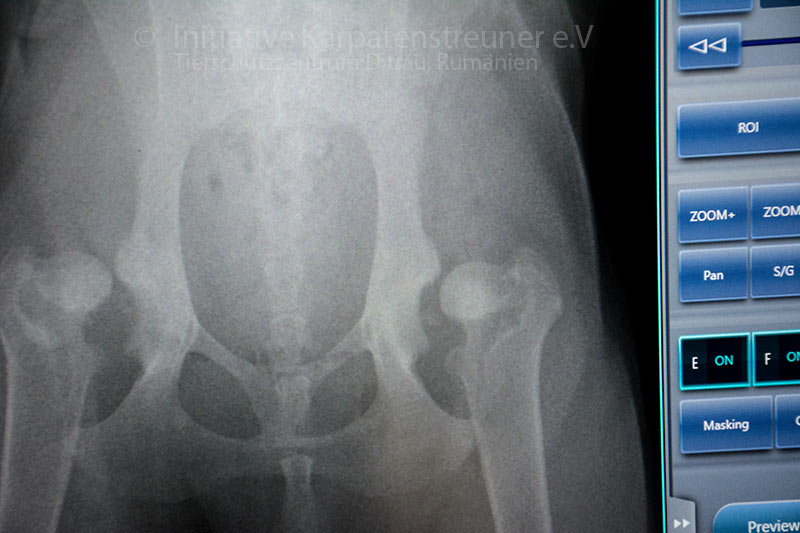

Wir hatten die Gelegenheit, die Tierarztpraxis von Equivent zu besuchen und waren mit Kaya, Inca sowie Ben dort. Die Röntgenaufnahme von Kayas Hüfte sieht leider mehr als schlecht aus. Sie hat hochgradig Hüftdisplasie (HD); die Gelenkpfannen sind nur ansatzweise zu erkennen. Eine Operation geschweige denn Behandlung durch Physiotherapie ist in Rumänien leider nicht machbar.